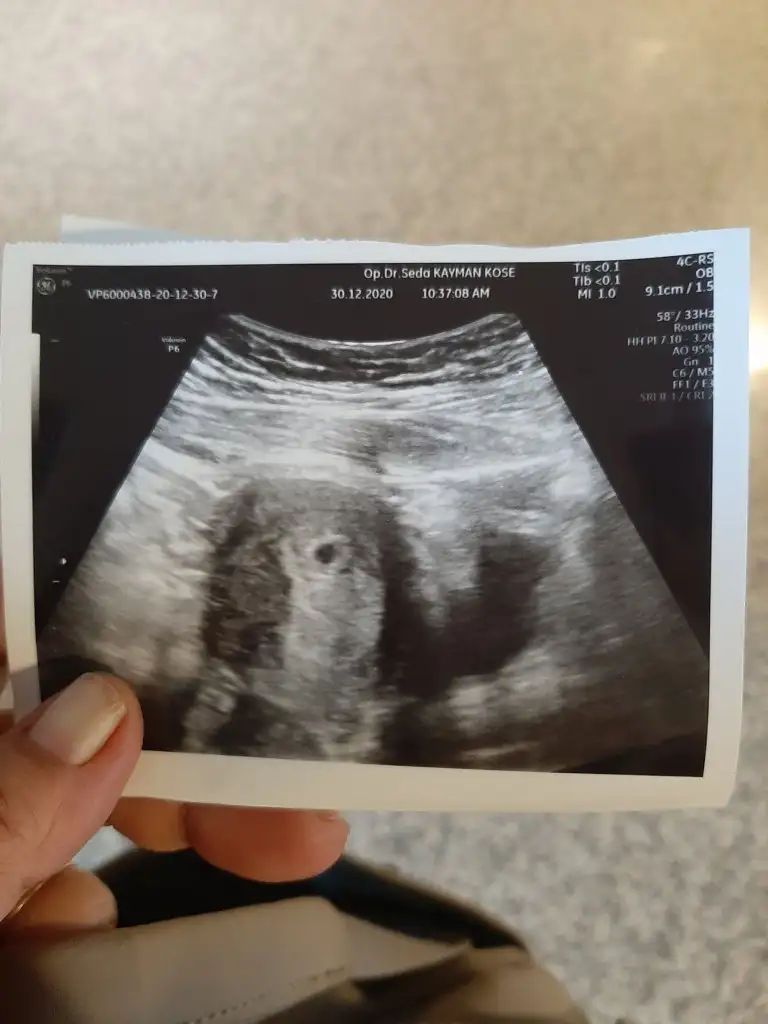

Yok sirz bekliyorumGördünmü bebişiniii

Gördünmü bebişiniii

Süper7. - 10. -12.günler şükür5 ocak a ultrason için çağırdı doktorum...

Benimde 5 ocak kalp atışı kese görünümü bebek görünümü hepsi olcak ilk ultrason7. - 10. -12.günler şükür5 ocak a ultrason için çağırdı doktorum...

Senin bebeğin daha büyükBenimde 5 ocak kalp atışı kese görünümü bebek görünümü hepsi olcak ilk ultrason